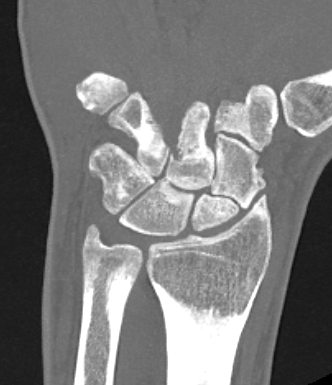

Definition

Scaphoid non union advanced collapse

Nonunion with resultant radiocarpal and midcarpal OA

Pathology

Scaphoid nonunion

- flexion deformity and abnormal joint mechanics

- radiocarpal osteoarthritis

- progresses from radial styloid / scaphoid fossa / midcarpal joint

- radiolunate joint preserved

Vender Classification

| Stage I | Stage II | Stage III |

|---|---|---|

|

Radial styloid and distal scaphoid fragment

+ Proximal scaphoid and capitate | + capitate-lunate joint |